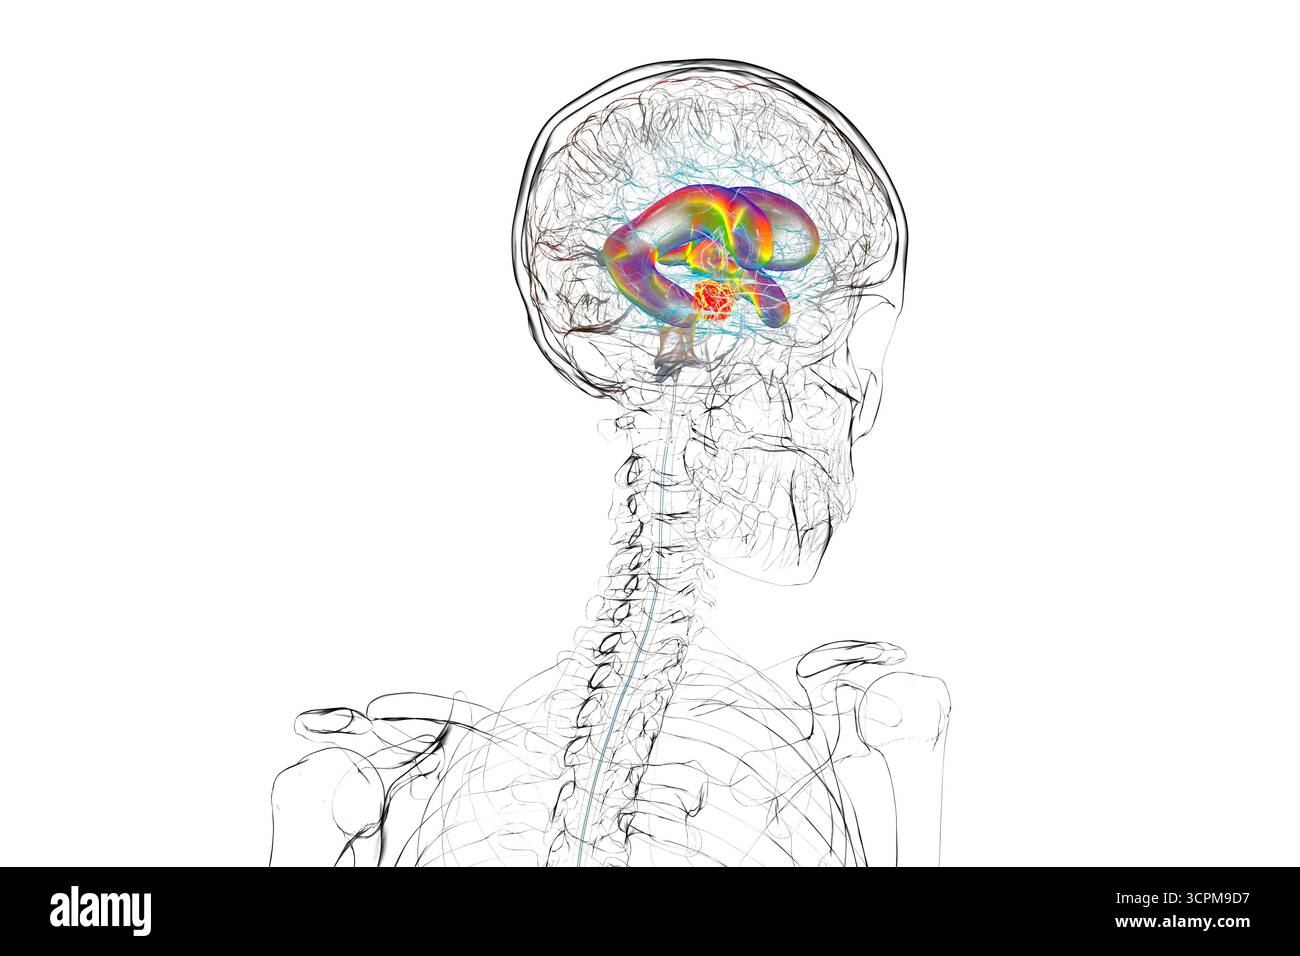

RF3CN8WHP–Illustration des vergrößerten lateralen und dritten Ventrikels des Gehirns (Hydrozephalus), hervorgerufen durch einen Hirntumor, der den Aquädukt des Gehirns komprimiert.

RF3CPM9C1–Illustration des dritten Hirnventrikels, einer lebenswichtigen Komponente des Hirnventrikulärsystems.

RF3CPM9BH–Illustration des dritten Hirnventrikels, einer lebenswichtigen Komponente des Hirnventrikulärsystems.

RF3CPM9BF–Illustration des dritten Hirnventrikels, einer lebenswichtigen Komponente des Hirnventrikulärsystems.

RF3CPM9BE–Illustration des dritten Hirnventrikels, einer lebenswichtigen Komponente des Hirnventrikulärsystems.

RF3CPM9BX–Illustration des dritten Hirnventrikels, einer lebenswichtigen Komponente des Hirnventrikulärsystems.